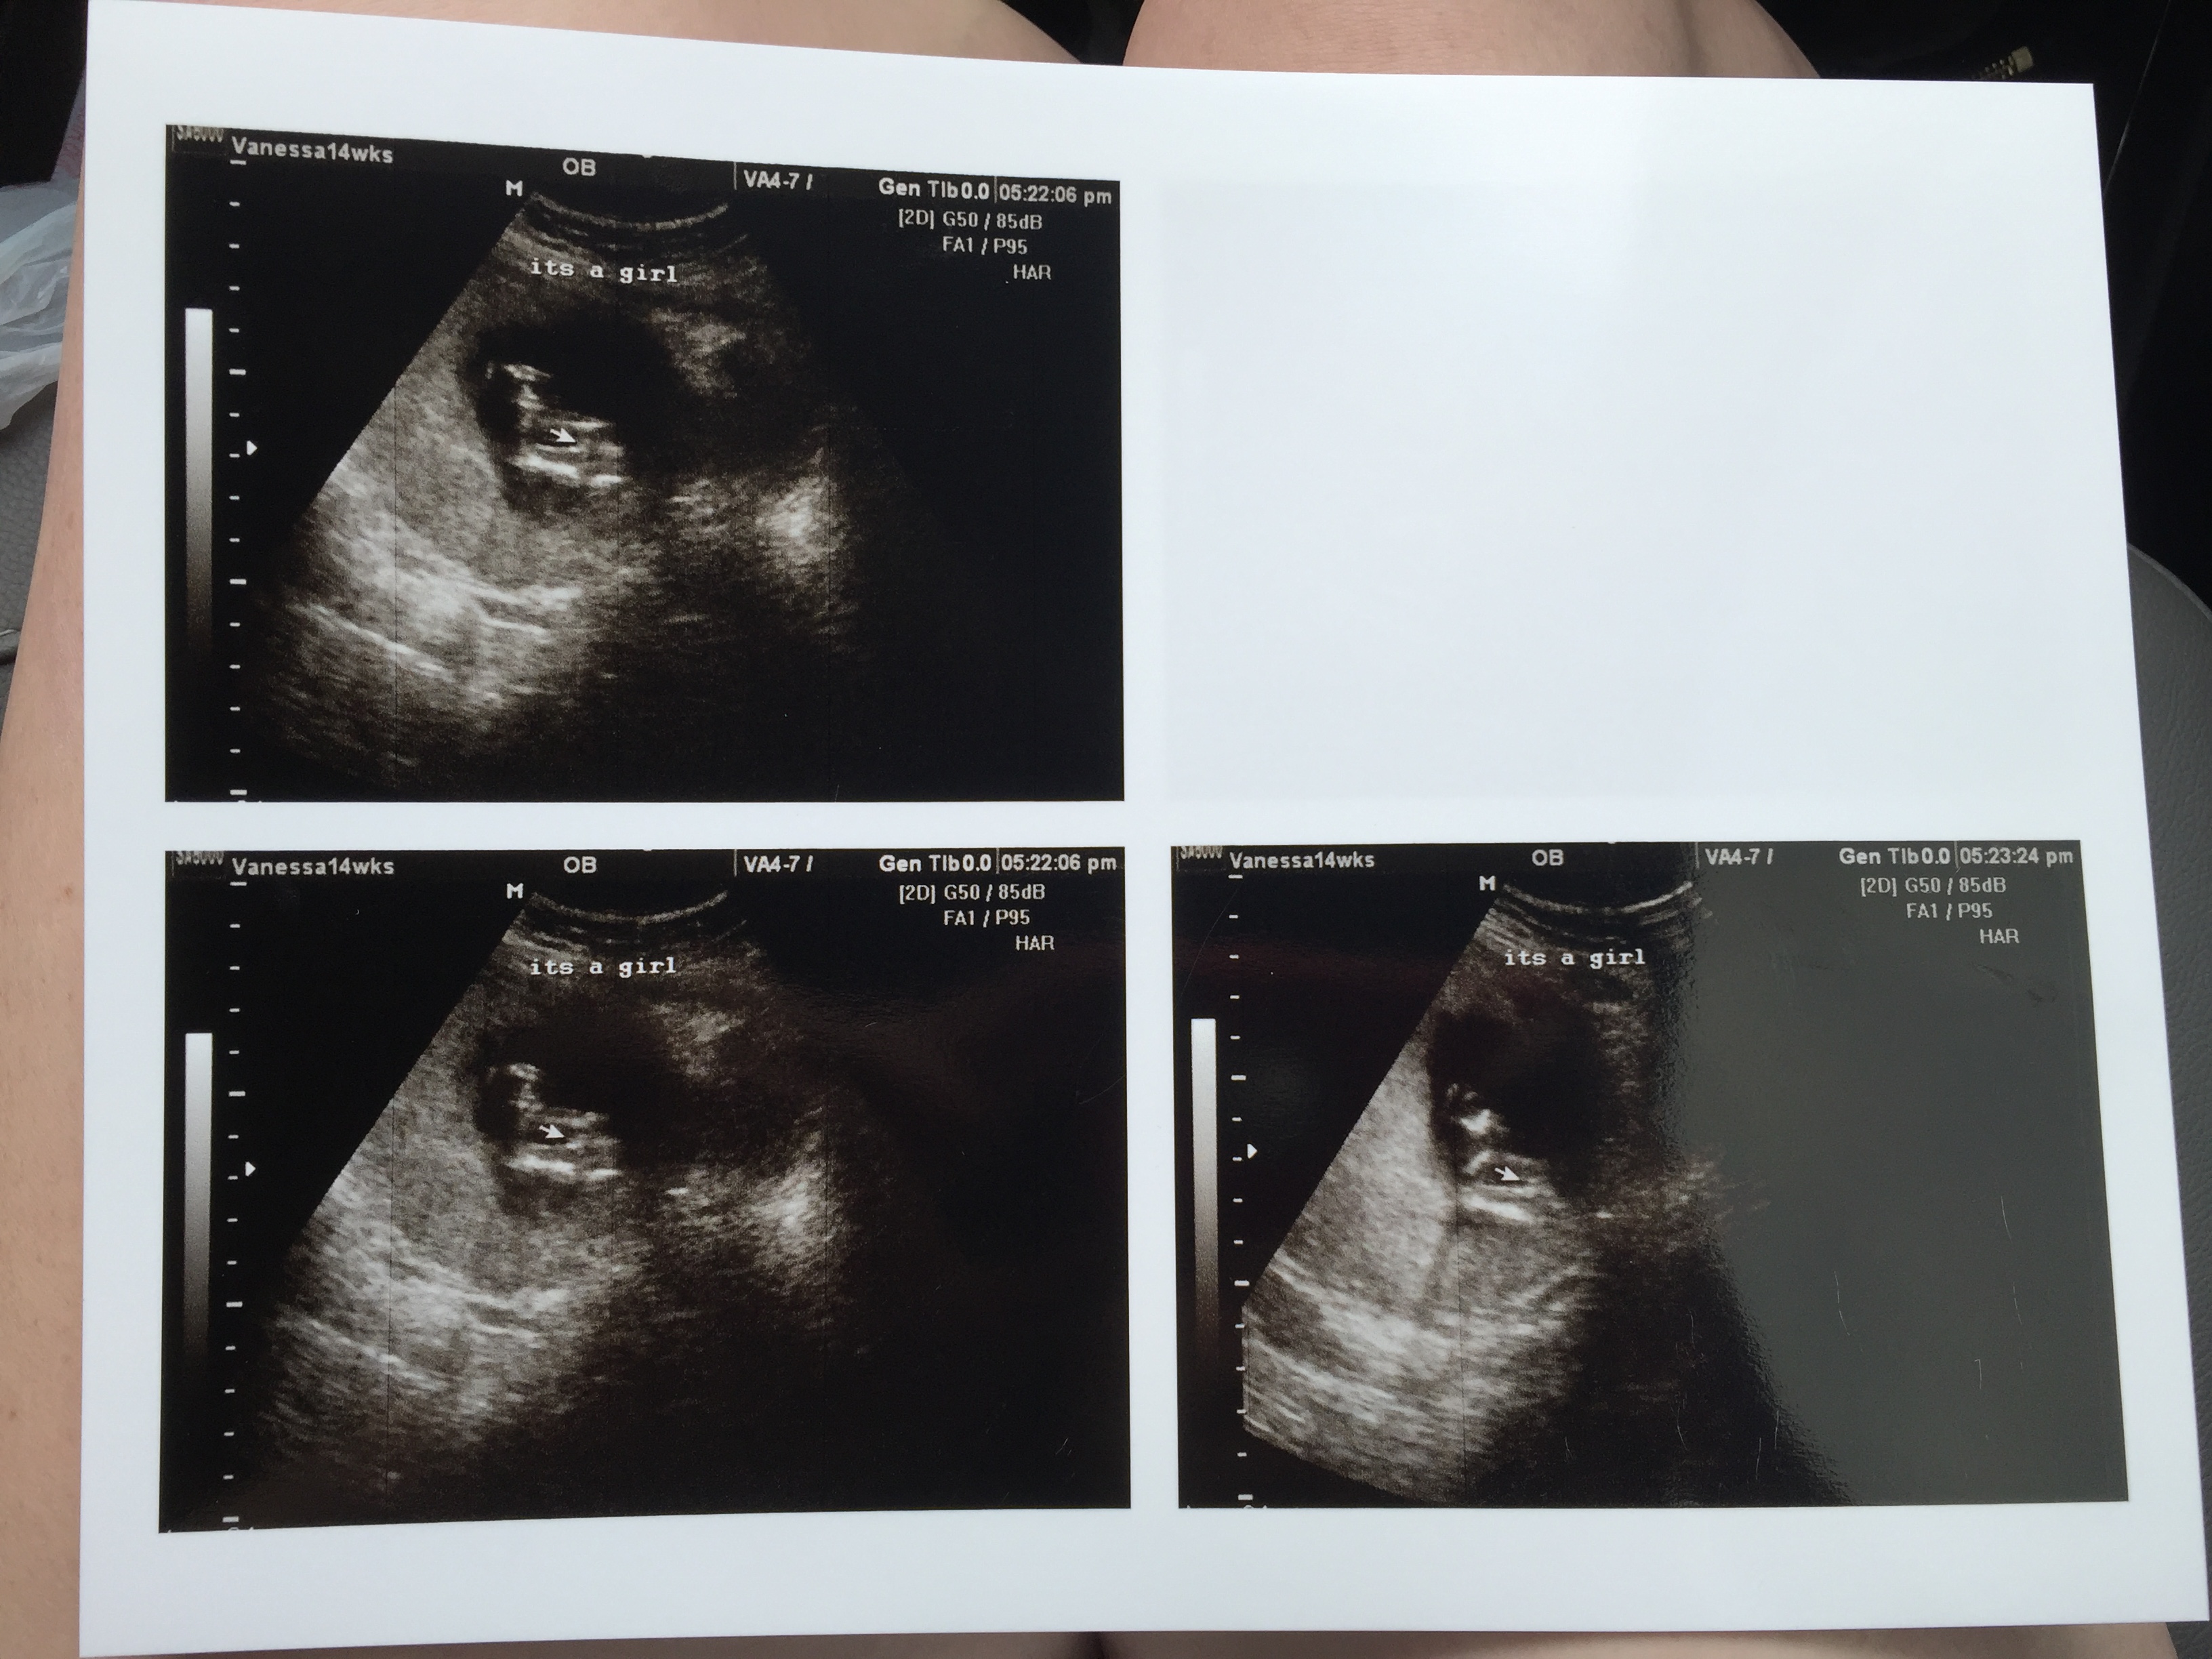

These are the best we could get because baby was VERY stubborn. Promising?Attachment 27753

It was a frustrating scan. I had to do a million jumping jacks, squats, laps around the building, etc because legs were crossed with cord in between! The tech said she suspected girl a few times during the scan but didn't say anything until she grabbed these shots.

That's exactly what the tech said lol. She said she's never had a boy be THIS modest. Ha! We got several different angles, did the blood flow numerous times to confirm cord, but never saw any boy bits trying to peak out. Unfortunately baby was in the worst position EVER and I was hoping for a nub, but she (I'm so reluctant to type that out) was being a stinker. Baby was laying upside down, diagonal with its butt crammed into the top corner of my uterus.